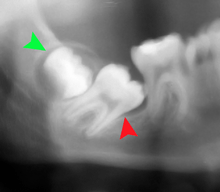

Coronectomy is a procedure used when the surgeon believes that there is a high risk of inferior alveolar nerve injury. After making the incision in the mucosa and removing bone adjacent the tooth, the crown is cut and removed with no attempt at removing the roots. It is indicated when there is no disease of the dental pulp or infection around the crown of the tooth and there is a high risk of inferior alveolar nerve injury.

Coronectomy, while lessening the immediate risk to the inferior alveolar nerve function has its own complication rates and can result in repeated surgeries. Between 2.3% and 38.3% of roots loosen during the procedure and need to be removed and up to 4.9% of cases require reoperation due to persistent pain, root exposure or persistent infection. The roots have also been reported to migrate in 13.2% to 85.9% of cases.[27]